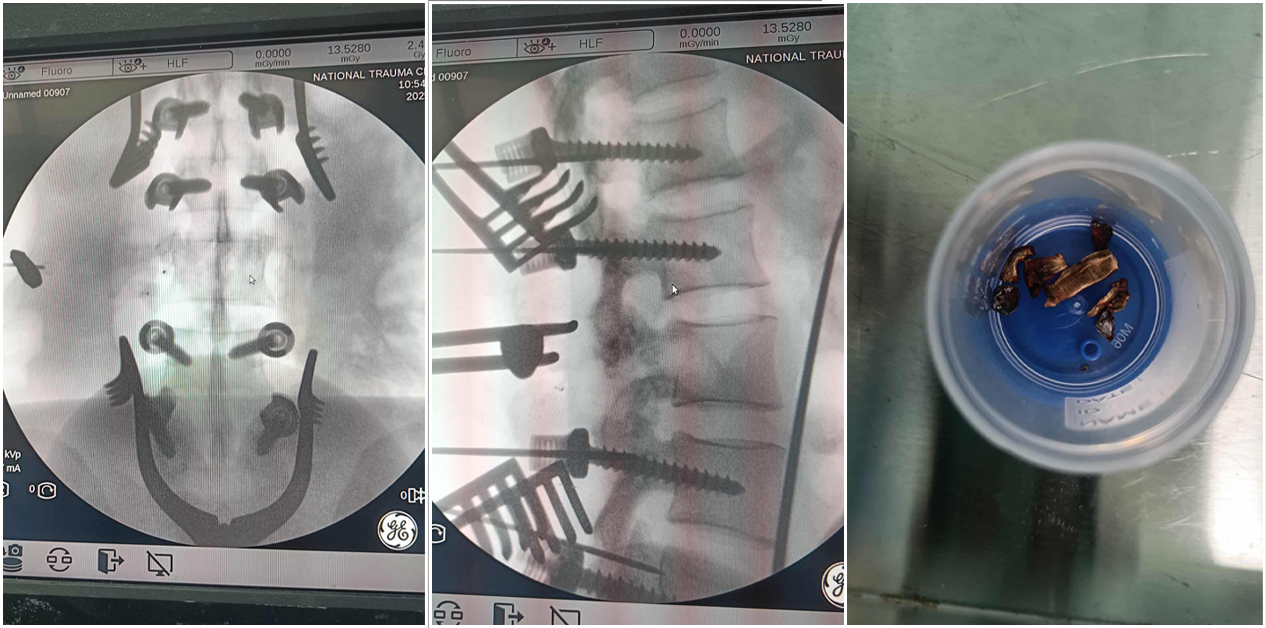

Following six hours of surgery, Pawan’s perforated intestine and bullet-punctured colon were treated. Doctors treating the injured protesters were themselves mentally affected by the complex conditions, bullets removed during surgery, wounds, and the statements of the injured. This was shared by Badri Rijal, head of the Trauma Center.